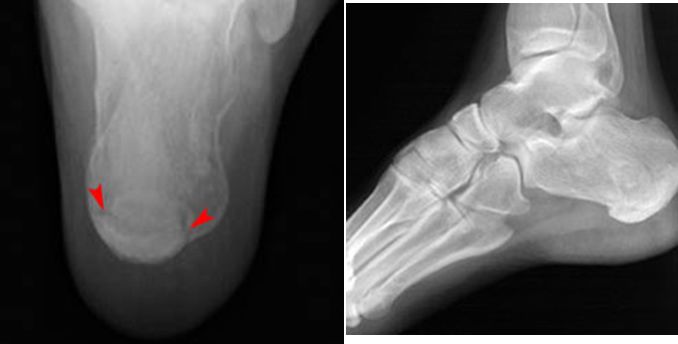

跟骨骨折

Jones Fracture

第五跖骨基底部骨折

易漏诊

不制动易致骨不连

跖骨骨折